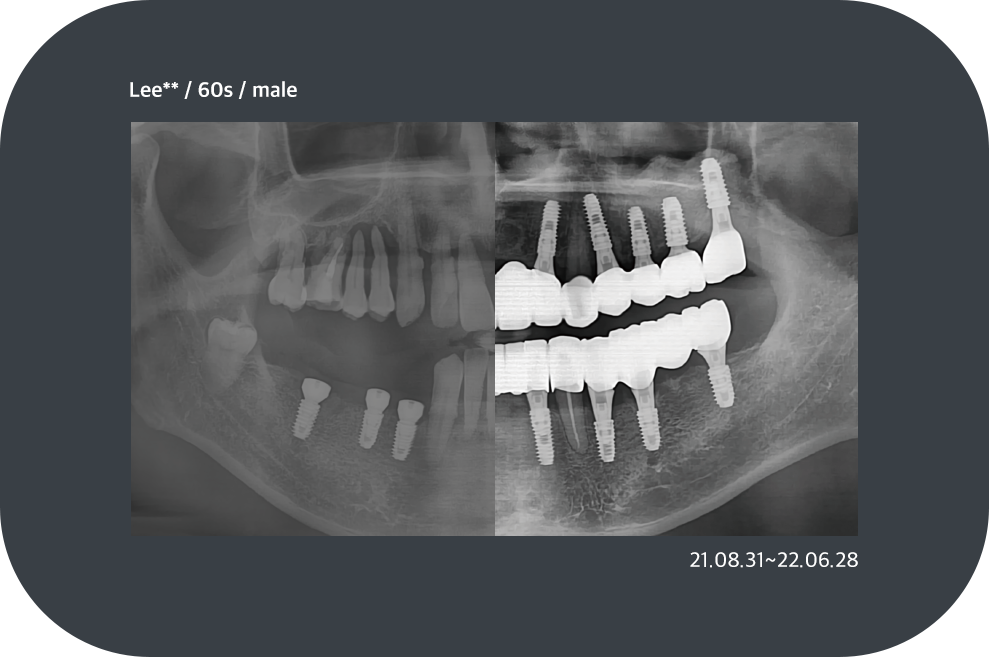

치료사례

임플란트 치료사례

implant_case01

implant_case02

implant_case03

implant_case04

*모든 증례 사진은 의료법 제23조, 제56조에 의거하여, 당사자의 동의하에 게시하였습니다.

*치료 사진은 모두 본원에서 치료한 환자분의 사진입니다.

*치료 사진은 모두 동일인의 사진이며, 동일조건에서 촬영하였습니다.

*개인의 차이에 따라 시술 및 수술 후 부작용이 발생할 수 있으며, 의료진과 충분한 상담을 받으시기 바랍니다.